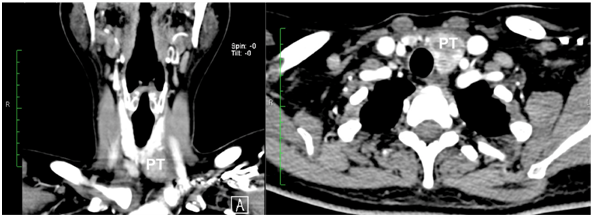

Based on these clinical, radiographic and laboratory results, the diagnosis of acute pancreatitis was made and the etiology of hypercalcemia was suspected. Further evaluation confirmed the primary hyperparathyroidism diagnosis, with elevated parathyroid hormone levels (iPTH: 462pg/ml, normal range 10-65pg/ml). Ultrasound and Tc-99m-sestamibi SPECT (single-photon emission computed tomography) scan examination demonstrated a solitary mass below the left lobe of the thyroid gland, compatible with lower parathyroid (Figure 1) (Figure 2). A head and neck computed tomography (CT scan) was performed; it showed an enlargement of the left thyroid lobule, but it was not clear if there was a parathyroid tumor (Figure 3). When the abdominal symptoms were completely controlled, the patient underwent surgical neck exploration finding a small left thyroid with a large brown polar nodule, which was sent for frozen section. Analysis confirmed an enlarge parathyroid gland adjacent to the left thyroid lobule, with local invasion of surrounding tissues (Figure 4). The decrease in serum calcium levels and normalization parathyroid hormone levels were confirmed postoperatively. At three and sevenmonths following surgery, the iPTH level was 34pg/ml, then 26pg/ml; calcium level was 8,7mg/dl, then 8,8mg/dl; phosphorus was 3,27mg/dl, then 3,32mg/dl, respectively.

Figure 3 Head and neck CT Scan, showed inferior polar nodule of the left thyroid lobule, finally it was consistently with a parathyroid tumor.

PT: left parathyroid.